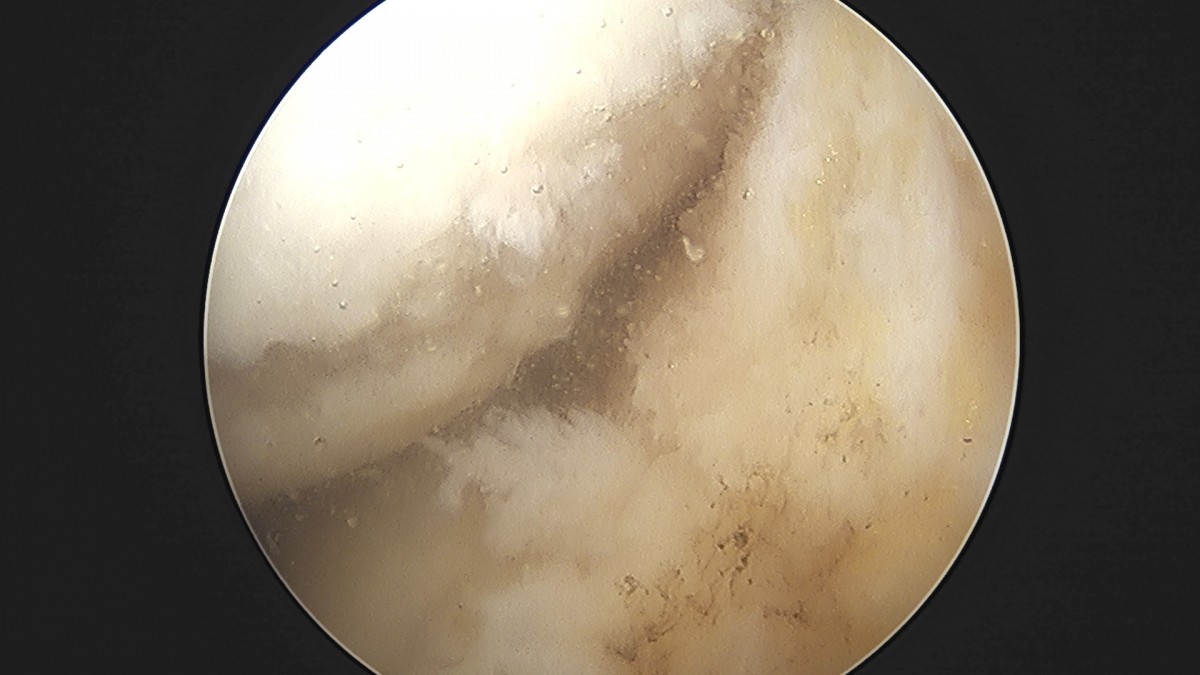

정지영원장님 무릎 반월상 연골판 절제술 이영O 환자

작성자 최고관리자 댓글 0건 조회 756회 작성일 25-09-16 16:56